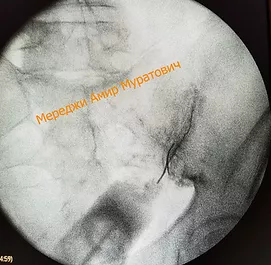

На рентгене справа показано положение иглы в полости крестцово-подвздошного сочленения и распределение контраста в полости сочленения.